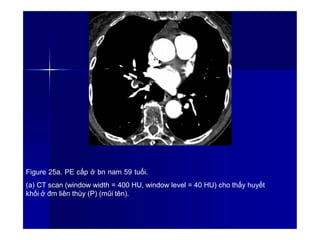

Figure 25a. PE cấp ở bn nam 59 tuổi.

(a) CT scan (window width = 400 HU, window level = 40 HU) cho thấy huyết

khối ở đm liên thùy (P) (mũi tên).

3